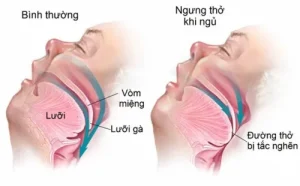

Bệnh nhiễm trùng đường hô hấp: Tổng quan về nguyên nhân, triệu chứng, cách điều trị và phòng ngừa hiệu quả để bảo vệ lá phổi của bạn

Chào bạn, hôm nay chúng ta sẽ cùng nhau tìm hiểu về một nhóm bệnh lý rất phổ biến mà hầu như ai cũng đã từng mắc phải ít nhất một lần trong